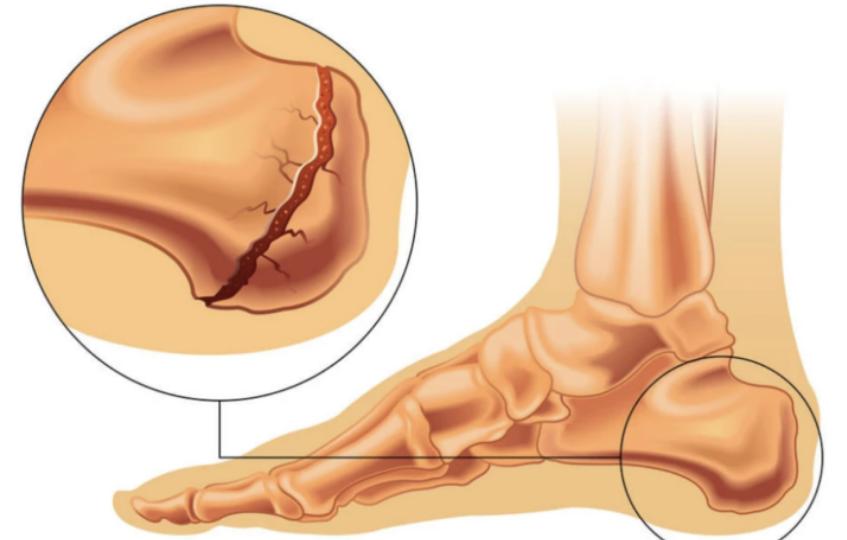

3、应力性骨折

应力性骨折,又被称为疲劳性骨折,可发生在脚底、脚后跟和脚背等部位。大部分应力性骨折是因为 长时间过度运动,使得骨头承受的压力太大或者时间太久,又没有适度的休息,导致骨头变得越来越脆弱,开始出现小的裂缝,只要稍微运动激烈点,脚部就会有剧烈疼痛感。

应力性骨折好发于 经常需要进行高强度、重复性机械运动的群体,例如专业运动员、舞蹈演员等。 另外,骨骼发育未完全的青少年,如果突然增大运动量,也可能会诱发应力性骨折。

应力性骨折早期,患者可能不会感到相关的疼痛,但疼痛感会逐渐加重。 休息的时候,症状会有所改善,但随着病情加剧,疼痛的区域会开始扩散。部分患者的疼痛处还可能会肿起来,严重时甚至整个脚都会肿。

临床上,一般的骨折可以通过X线检查来诊断,但轻至中度的应力性骨折早期可能不一定能从X线片中看得出来。 如果高度怀疑是应力性骨折,但X光又看不出时,就要做磁共振成像检查,可以有效发现骨膜和骨髓水肿范围。